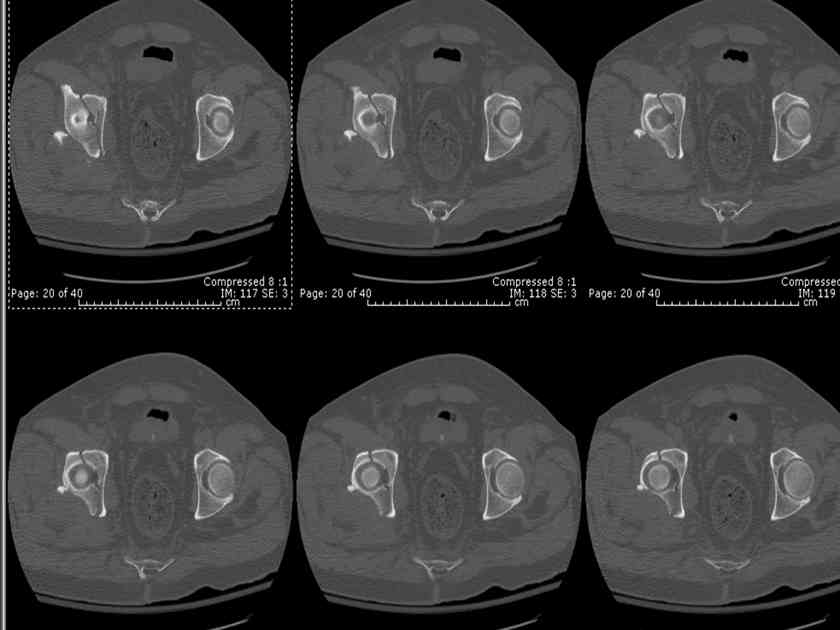

The 2nd example is of a motorcyclist with a transverse fracture-dislocation...he had a closed attempted reduction and placed in traction but the manipulative reduction was not concentric (not unusual for this injury pattern)...so the traction was adjusted to be just enough to disengage the head from the fracture (12#) until he could be cleared for surgery one day after injury...he was treated "urgently" then with a prone KL, clean the fracture, reduce and clamp it, screw it, support with a balanced plate, close, and enjoy...2-3hours, 400cc EBL, blah, blah, blah..

If you¹d examine any routine CT scan of a normal non-variant pattern transverse fracture, and imagine where you¹d place your ideal clamp for compression of the fracture line, then it¹s typically with one tine applied to the quadrilateral surface and the other tine applied in the area between the AIIS and the posterior wall (or the wall itself in some instances)... the

If you¹d simply elevate the periosteum of the greater notch, then work thru the notch to elevate the obturator internus from the quadrilateral surface, then you can palpate thru the notch the transverse fracture offset/displacement at the quadrilateral surface and often all the way to

the anterior column. You can then lateralize/lengthen the caudal transverse segment uniformly however you¹d choose and clamp it thru the notch... then palpate thru the notch to better assess the near entirety of the transverse fracture... the C-arm images confirm the restoration of the 3 line landmarks and you can adjust the C-arm beam to be tangential to the true fracture line if you¹re still in disbelief that you¹ve finally gotten a transverse reduction!! The transverse¹s anterior column component can next be